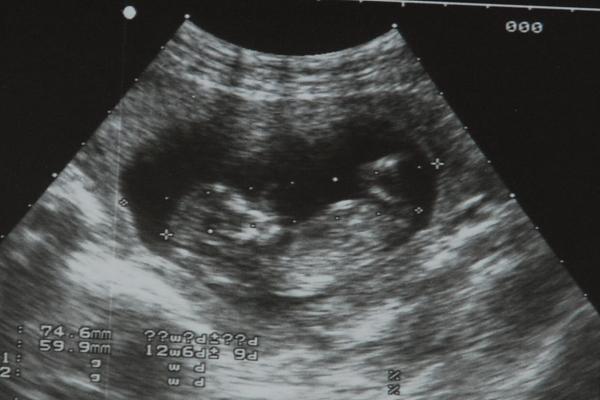

Narodil se nám Toníček 😵